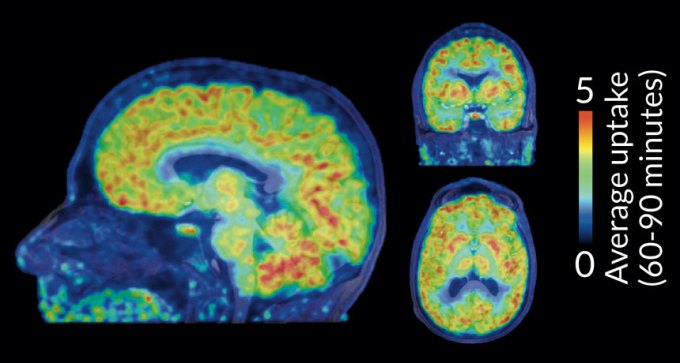

27. Genetics

Scientists get a glimpse of chemical tagging in live brains

For the first time scientists can see where molecular tags known as epigenetic marks are placed in the brain.